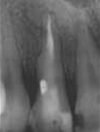

Trattamento endodontico laser assistito